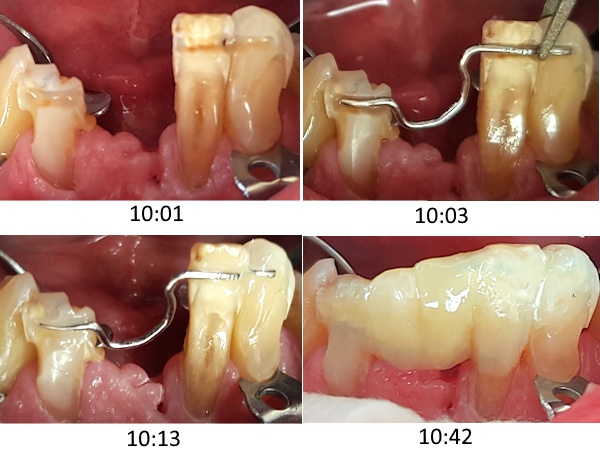

82-jähriger Patient (18.03.2026 / 457)

Der Patient hat einen extrem tiefen Deckbiss und beisst sehr kräftig. Die Zahnlücke stört ihn sehr.

Die drahtverstärkte Kompositbrücke ist innert einer Stunde hergestellt, hat 580 CHF gekostet, und wird jeder Belastung durch den Deckbiss standhalten.

Eine Voraussetzung für eine solche Klebebrücke aus Komposit ist das geschickte handwerkliche Verbiegen des Drahtes.